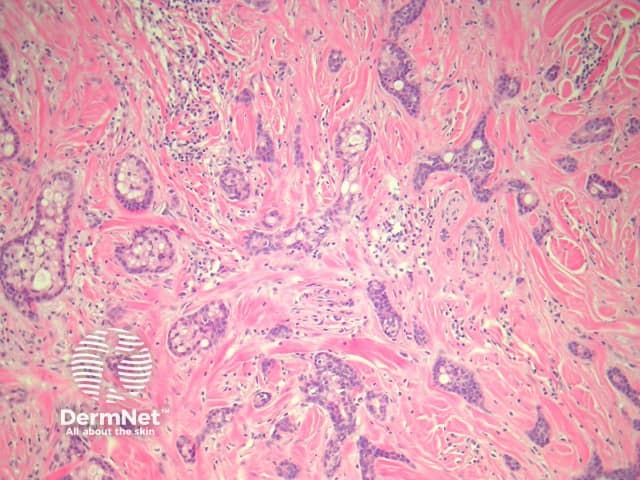

Sections of eccrine carcinoma show a tumour composed of basaloid cells infiltrating the dermis (figure 1). The tumour forms tubules and glands (figures 2-4) which infiltrate a sclerotic dermis. Eccrine differentiation is readily seen at high power (best seen in figures 2 and 3). Clear cell change may be seen (figure 4).

Figure 3

Figure 4